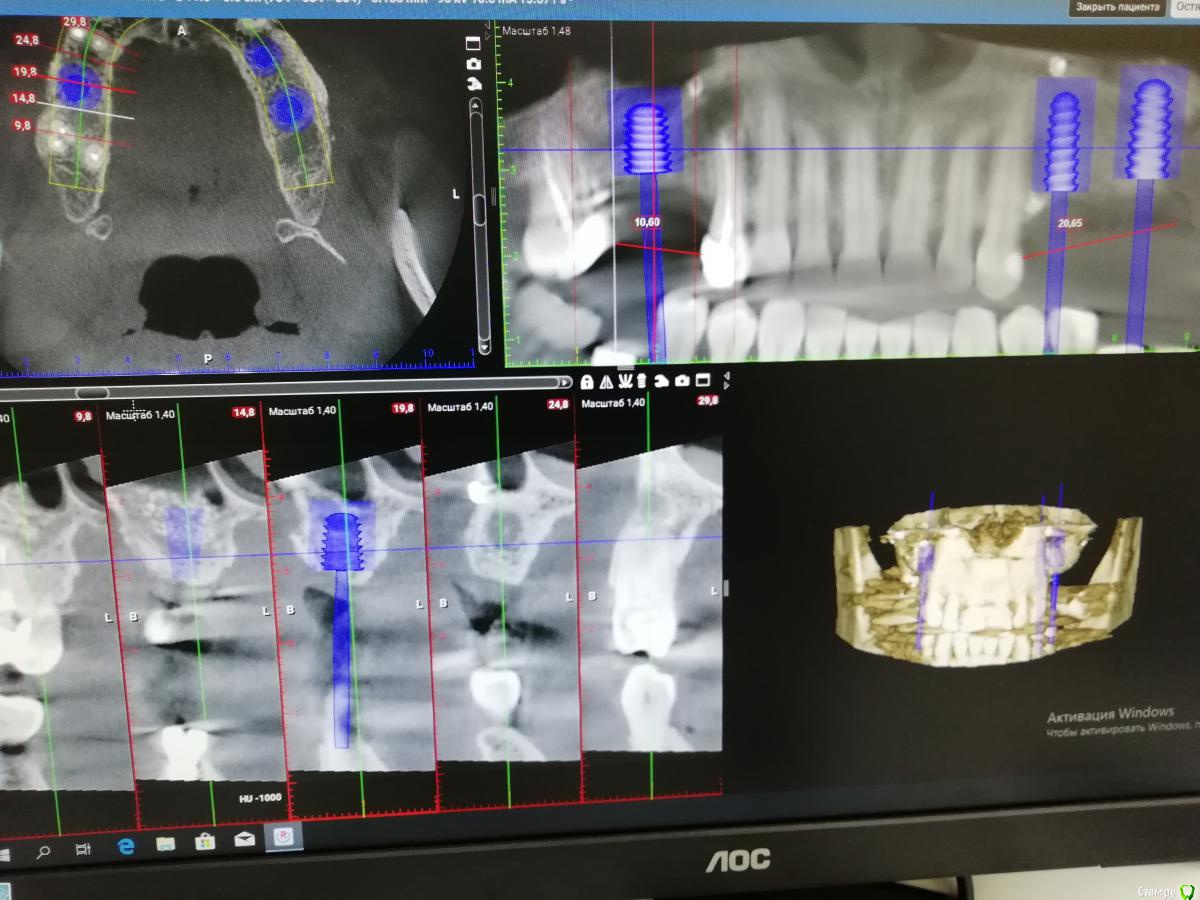

___49___ Опубликовано 23 декабря, 2019 Автор Поделиться Опубликовано 23 декабря, 2019 Планирую Импланты:обл16 - 6х8 обл 24- 4.5х12обл 26- 6х12 Коментарии, критика , свое виденье планирования уважаемые коллеги высказывайте. Спасибо . Ссылка на комментарий

___49___ Опубликовано 7 января, 2020 Автор Поделиться Опубликовано 7 января, 2020 (изменено) Во вотором секторе лунка удаленного зуба выглядит пустой. Метериал не вносили? Во втором секторе , 27 зуб был удален полсе НКР через 4.5 месяца, лунка (благодаря НКР) теперь имеет все 4 стенки , так как графт был в контакте с зубом 27 (который временно выполнял роль дополнительной стенки) он мог быть обсеменен, свободно лежащие частички графта я убрал и заложил губку на линкомицине - так же максимально желая предотвратить возможное инфицирование графта , но при этом сильно не потерять в кости - чего и добился - фото с расставленными имплантами через 1-2 месяца после удаления 27 го. Что касается губки - она очень хорошо прорастает молодыми сосудами , что играет большое значение в трофике оставшейся кости,а также новой (ксено +ауто) - это сугубо мой личный вывод(не факт что верный) Изменено 7 января, 2020 пользователем ___49___ Ссылка на комментарий